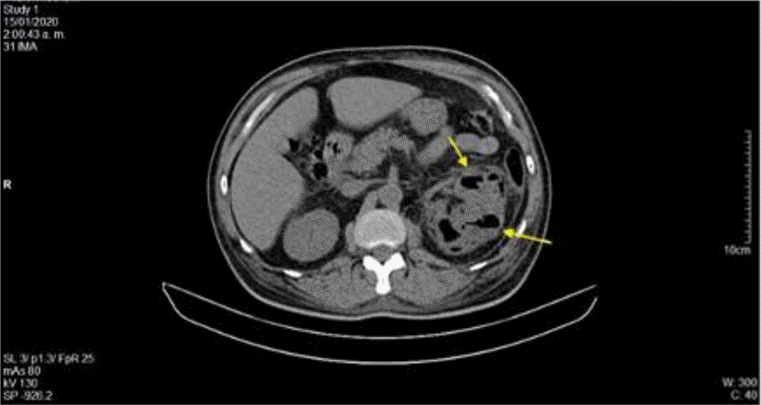

La ecografía abdominal total mostró hallazgos sugestivos de PNE izquierda (Figura 1), por lo que se solicitó valoración por urología; este servicio indicó continuar con la misma terapia antibiótica y realizar UROTAC que mostró microlitiasis renal bilateral, litiasis ureteral izquierda y proceso infeccioso inflamatorio con presencia de gas en el riñón izquierdo, lo que indicó diagnóstico de PNE izquierda tipo 2 (Figuras 2 y 3). Ante los hallazgos radiológicos y el reporte de urocultivo positivo para Escherichia coli multisensible, se decidió hacer rotación de cubrimiento antibiótico a carbapenémicos debido al alto riesgo de mortalidad.